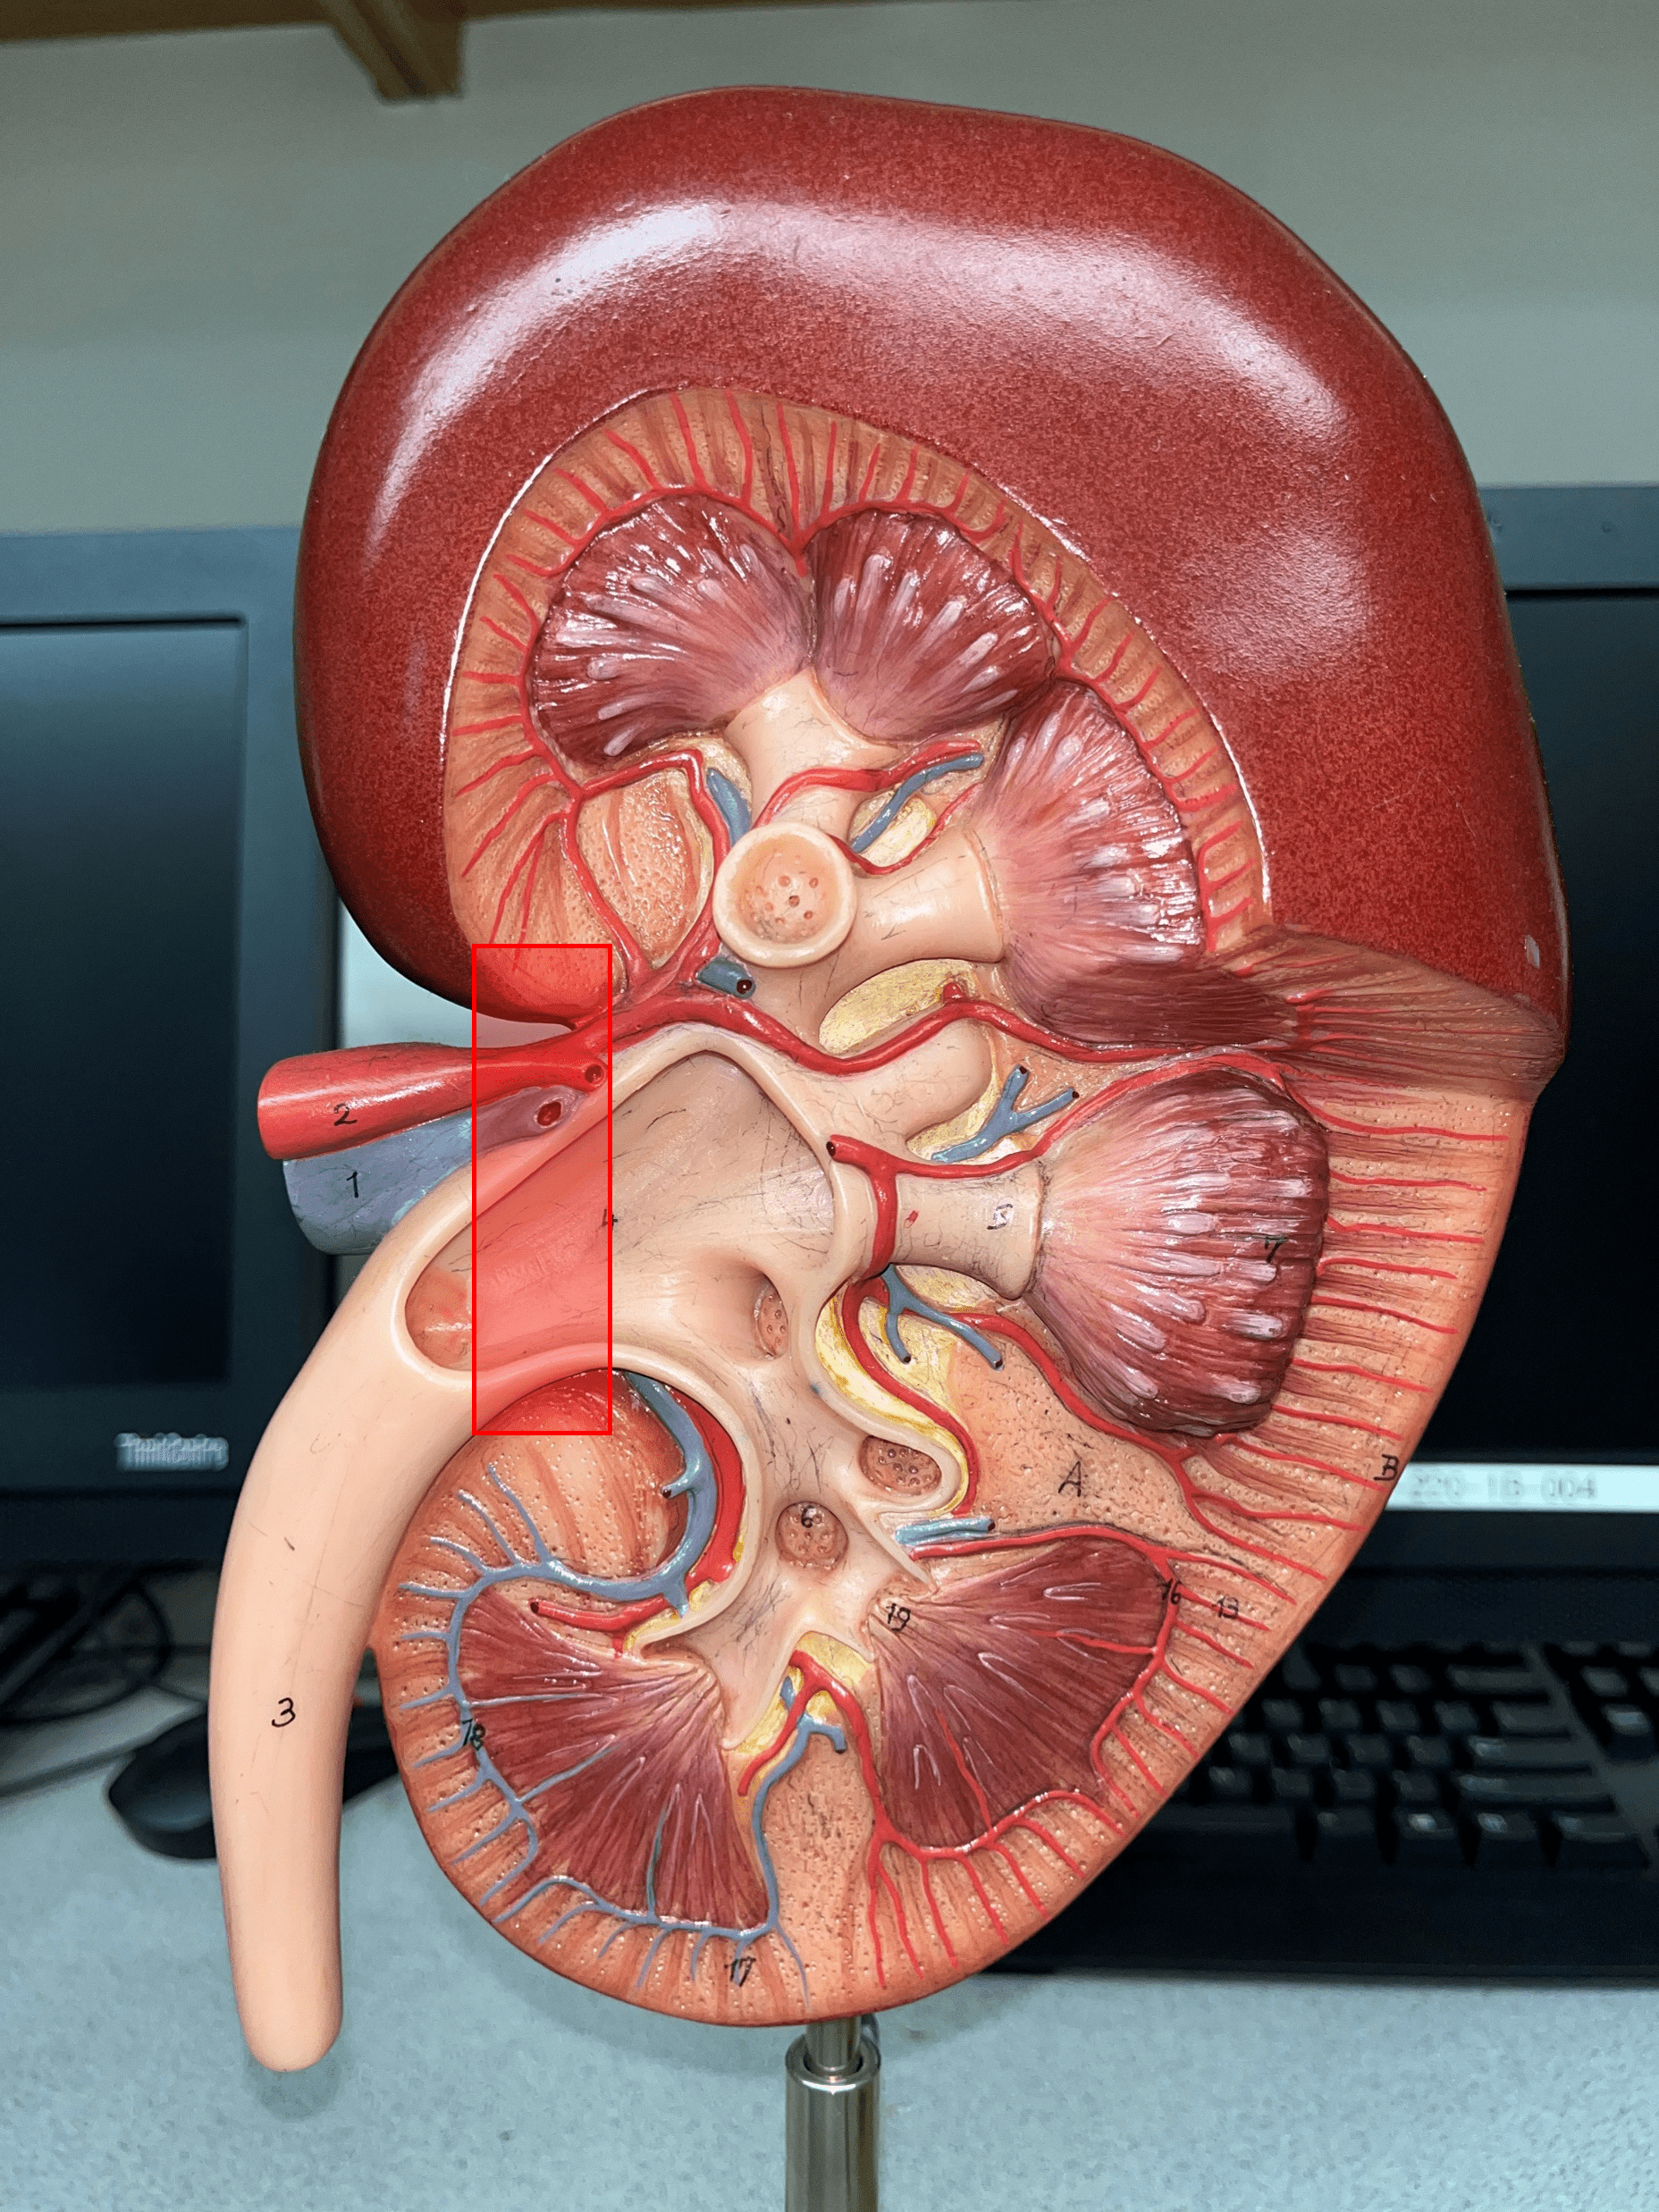

renal artery

• The largest a. of the kidney.

• Supplies the entire kidney.

• Branches into smaller segmental aa.

• Supplies the entire kidney.

• Branches into smaller segmental aa.

segmental artery

• Branches of the renal a.

• Branches into smaller interlobar aa.

• Branches into smaller interlobar aa.

renal vein

• The largest vein of the kidney.

• Drains blood from the entire kidney.

• The convergence of interlobar vv.

• Drains blood from the entire kidney.

• The convergence of interlobar vv.

ureter

• A narrow tube channeling urine from the kidneys to the urinary bladder.

renal hilum

• The concavity of the kidney.

• Admits the ureters, renal a., renal v., lymphatics, and nerves.

• Also known as the hilus of the kidney.